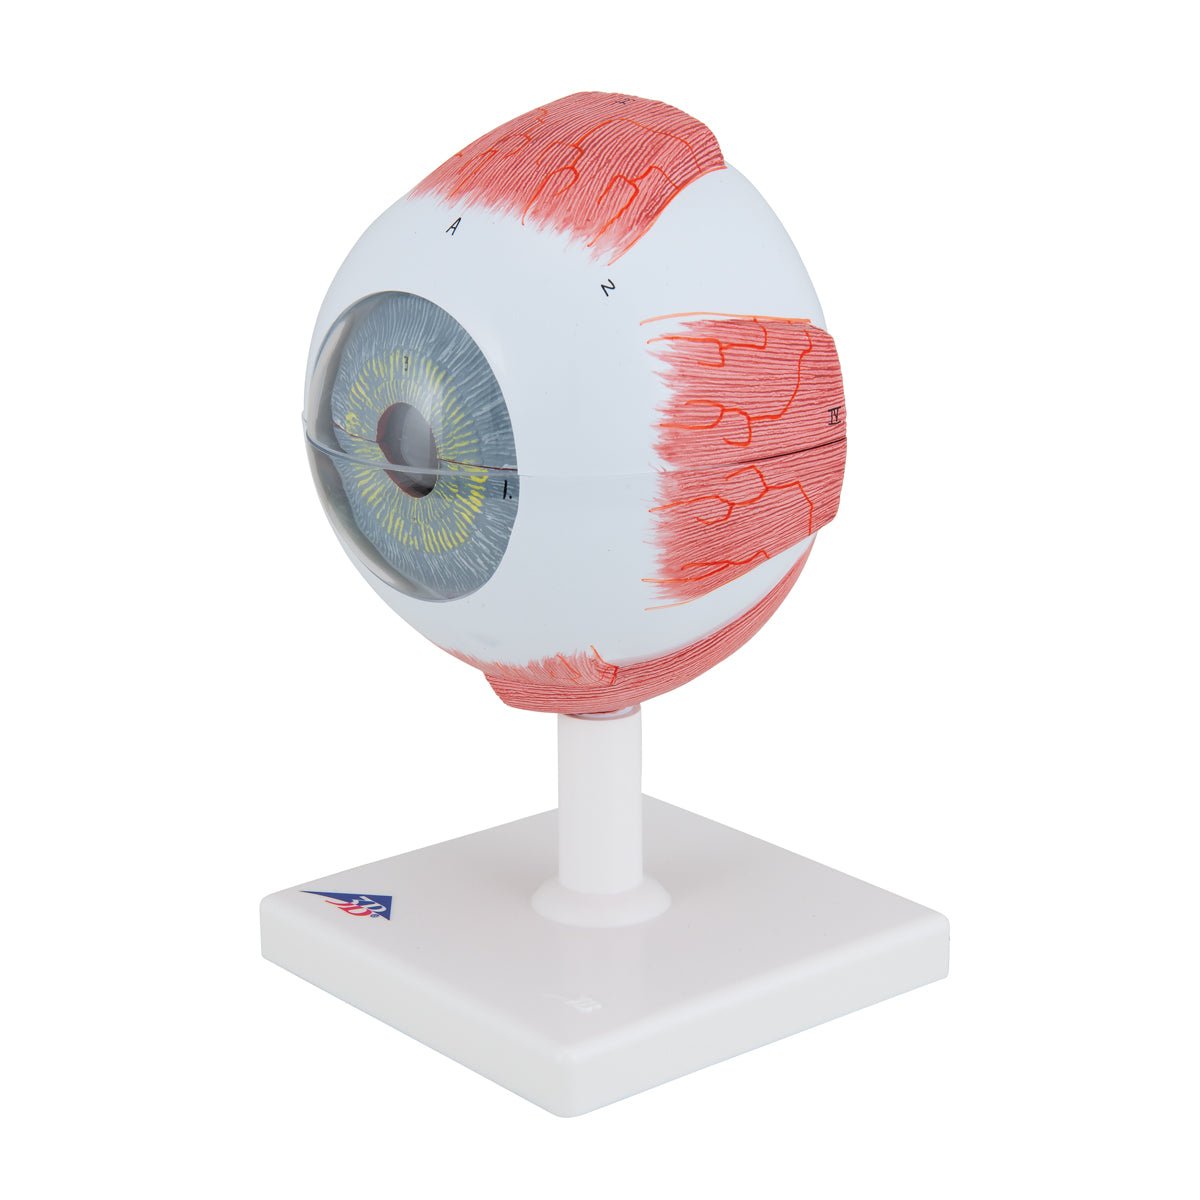

Anatomical models

Selling anatomical models is the mainstay of eAnatomi, although we also spend a lot of resources developing our own anatomical materials such as posters. Anatomical models are used for various purposes and can show both defined tissues, organs and organ systems. Are you looking for a simple model of bone tissue or perhaps an advanced torso model based on MRI technology, you can find it all at eanatomi.com.